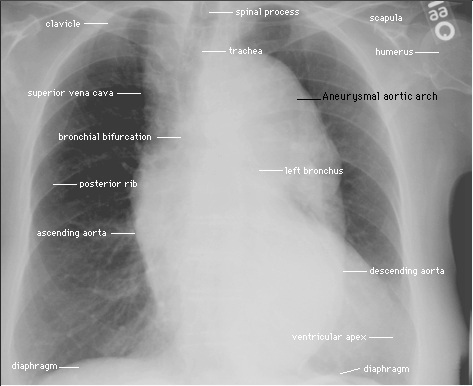

Radiografia del Torace: nelle proiezioni anteroposteriore e laterale che dimostrano uno slargamento dell’ombra mediastinica con evidente dilatazione aortica.